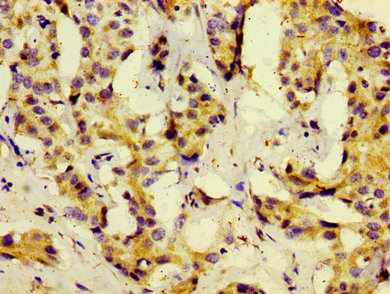

圖片:

應用范圍:ELISA, IHC

Application Recommended Dilution IHC 1:20-1:200 -